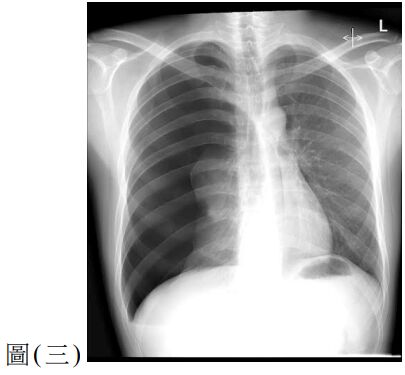

10. 一位 60 歲女性因腹痛、噁心與嘔吐來急診。此病人有剖腹產與膽囊切除手術病史,其 KUB如圖(二),請問最有可能的診斷為何?

(A) 沾黏性小腸阻塞( adhesive small bowel obstruction ) (B) 大腸阻塞(large bowel obstruction ) (C) 缺血性大腸炎(ischemic colitis) (D) 小腸憩室炎(small bowel diverticulitis)